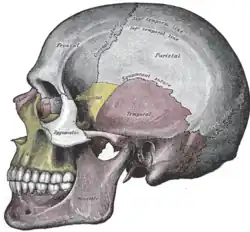

Ossos faciais

Ossos faciais -

Vista lateral

Vista lateral -

Vista lateral do crânio

Vista lateral do crânio -